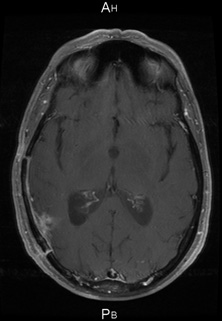

Mars 2011 Juin 2011

Mars 2011 : Patiente de 59 ans porteuse d’un glioblastome avec hémiplégie gauche ne permettant plus la marche.

D’avril 2011 à juin 2011 : bévacizumab 10 mg/kg en IV tous les 15 jours et témozolomide (150 puis 200 mg/m2/jour x 5 jours) à 4 semaines d’intervalle.

Récupération complète de l’hémiplégie.

Juillet/août 2011 : Radiochimiothérapie selon ‘’Stupp’’ en poursuivant le BVZ pendant la radiothérapie

Octobre 2011. Aucun déficit neurologique. OMS 0. Temozolomide adjuvant en cours et bévacizumab tous les 15 jours.